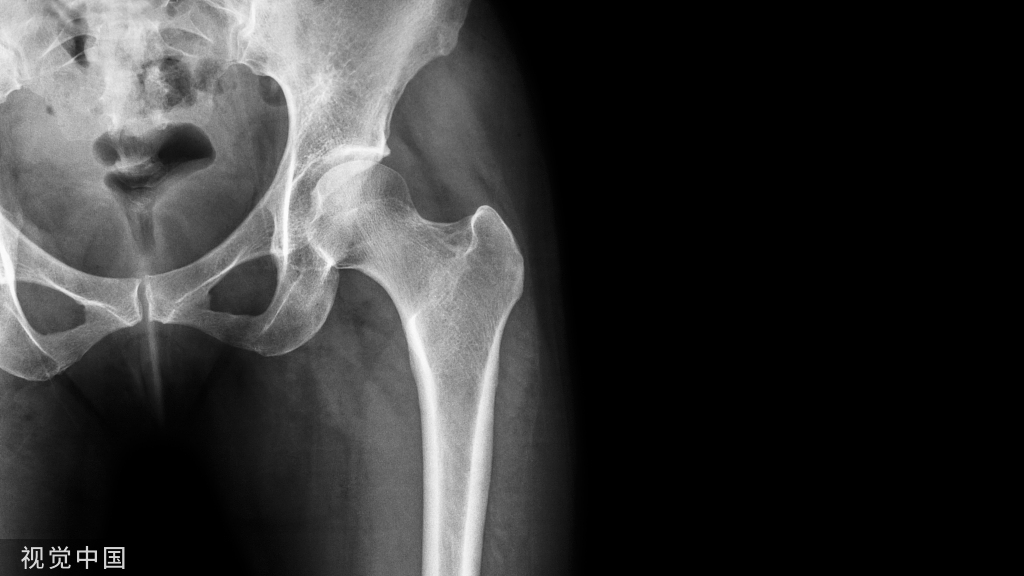

膝关节穿刺术常用于检查关节腔内积液的性质,或抽液后向关节腔内注药。膝关节腔内积液,需行关节穿刺抽液检查或引流,或注射药物进行治疗。关节腔内注射空气或造影剂,行关节造影术,以了解关节软骨或骨端的变化。